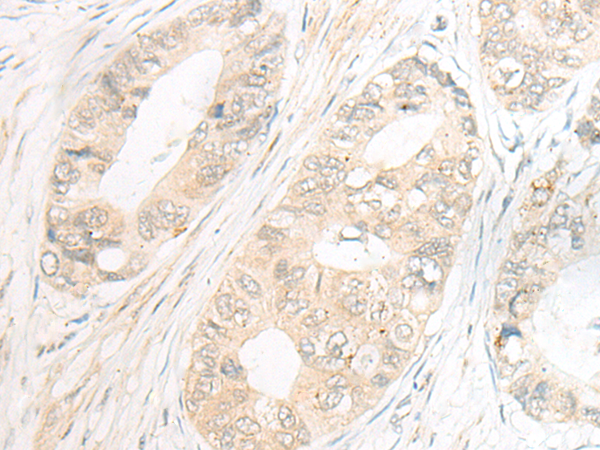

分类: 科研抗体货号: P06421别名: EIF3S1; eIF3-p35; eIF3-alpha应用: WB,IHC反应种属: Human, Rat